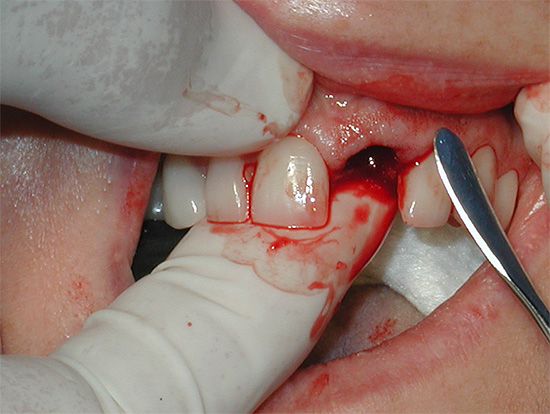

Tratamento profissional da alveolite: o que você pode esperar no consultório do dentista

Quando os pacientes consultam um cirurgião-dentista sobre a inflamação do orifício após o procedimento de extração dentária, o médico geralmente vê a seguinte imagem na cavidade oral: o coágulo sanguíneo no orifício está completamente ausente ou há resíduos em decomposição; com pressão na gengiva, podem ser liberados pus com odor desagradável. Isso geralmente é suficiente para diagnosticar "alveolite" e prosseguir com seu tratamento imediato.

O tratamento da alveolite após a extração dentária consiste em várias etapas:

- Primeiro, é dada boa anestesia;

- É realizada a curetagem (limpeza) do orifício do dente extraído - ele é raspado com tratamento mecânico completo dos tecidos necróticos enquanto lava a ferida com soluções de anti-sépticos de restos de comida, saliva, coágulo deteriorado, etc;

- Em seguida, o buraco é atualizado com um bisturi;

- De acordo com o depoimento, as costuras são sobrepostas no buraco, um guardanapo de gaze é instalado com ou sem a droga;

- Recomendações para o tratamento de feridas são fornecidas e são prescritos enxaguatórios e medicamentos anti-sépticos para aplicação tópica na forma de géis ou pomadas.